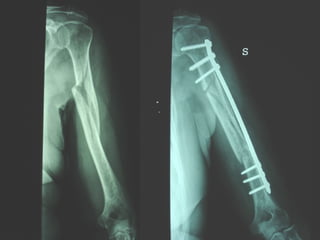

Dal Gennaio 2000 al Febbraio 2006 abbiamo trattato 167 fratture chiuse  con placca percutanea  in 164 pazienti :  27 lesioni diafisarie di gamba, 12 piloni tibiali ,  11 fratture prossimali di tibia, 36 fratture sovracondiloidee di femore, 17 fratture diafisarie di femore, 43 fratture metaepifisarie prossimali di omero, 21 diafisarie d’omero.  156 guarigioni 8 fallimenti

I buoni risultati ottenuti dipendono da 5 punti fondamentali:   una accurata riduzione percutanea della frattura  precise vie di accesso  l’utilizzo della placca che consenta il più lungo braccio di leva possibile il pretensionamento della placca  una sintesi con un ridotto numero di viti

Precise vie di accesso

Placche lunghe e pretensionate

Placche lunghe e pretensionate Sintesi con un ridotto numero di viti